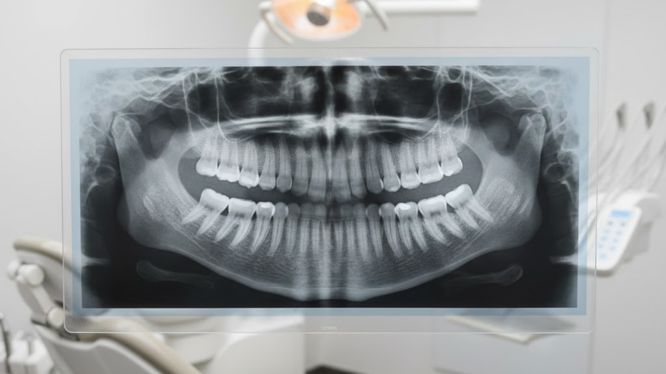

🔹 Radiografía panorámica

Es la radiografía dental más utilizada.

Permite valorar en una sola imagen:

• Todos los dientes

• Maxilar y mandíbula

• Articulaciones (ATM)

• Procesos inflamatorios

• Lesiones traumáticas o patológicas

📌 Se recomienda cuando:

• Hay dolor general

• Evaluación inicial

• Muelas del juicio

• Ortodoncia

• Planeación de tratamientos

Radiografía panorámica